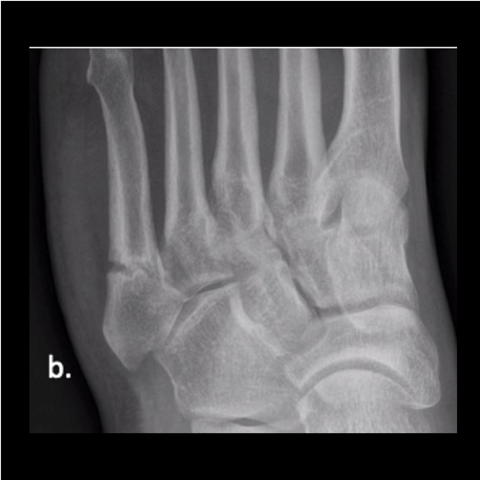

Figure 3a

Figure 3a. A 28-year-old Army officer injured during combatives was able to walk 2 days post-surgery. He started wearing his Army boots 2 weeks after surgery and completed Sapper School 10 weeks after surgery. He then went to Special Forces training within 6 months postop. The patient never had any pain after surgery. Here is the foot when the patient got injured.

Figure 3b

Figure 3b. A 28-year-old Army officer injured during combatives was able to walk 2 days post-surgery. He started wearing his Army boots 2 weeks after surgery and completed Sapper School 10 weeks after surgery. He then went to Special Forces training within 6 months postop. The patient never had any pain after surgery. Here is the foot when the patient got injured.